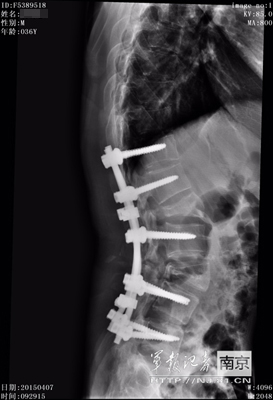

術(shù)前術(shù)后CT對比